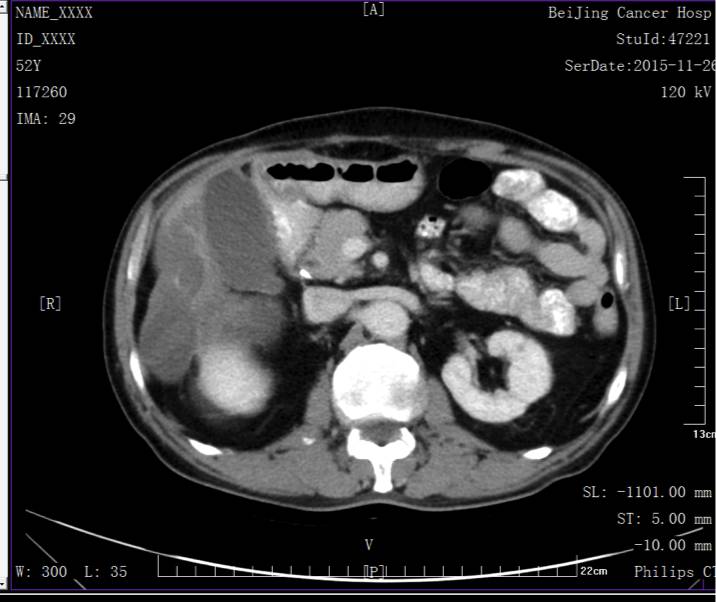

定期复查未见复发转移。

末次复查日期2015.11.18。腹盆部CT、胸片未见异常。

本例患者横结肠癌术后,肝转移同时伴有腹腔转移,肝转移单发、不足5cm、肝外转移不位于肝门或腹膜后,按照在本期《Colorectal Cancer Liver Metastases andConcurrent Extrahepatic Disease Treated With Resection》一文中提到的评分标准,本患者为1分(肝转移大约3cm)。进行手术切除后,术后进行了FOLFIRI方案的辅助化疗。DFS约7个月,再次出现了胰头后复发,再次评分本患者为1分(胰头后淋巴结),为患者再次选择手术切除。目前患者DFS已超过4年。